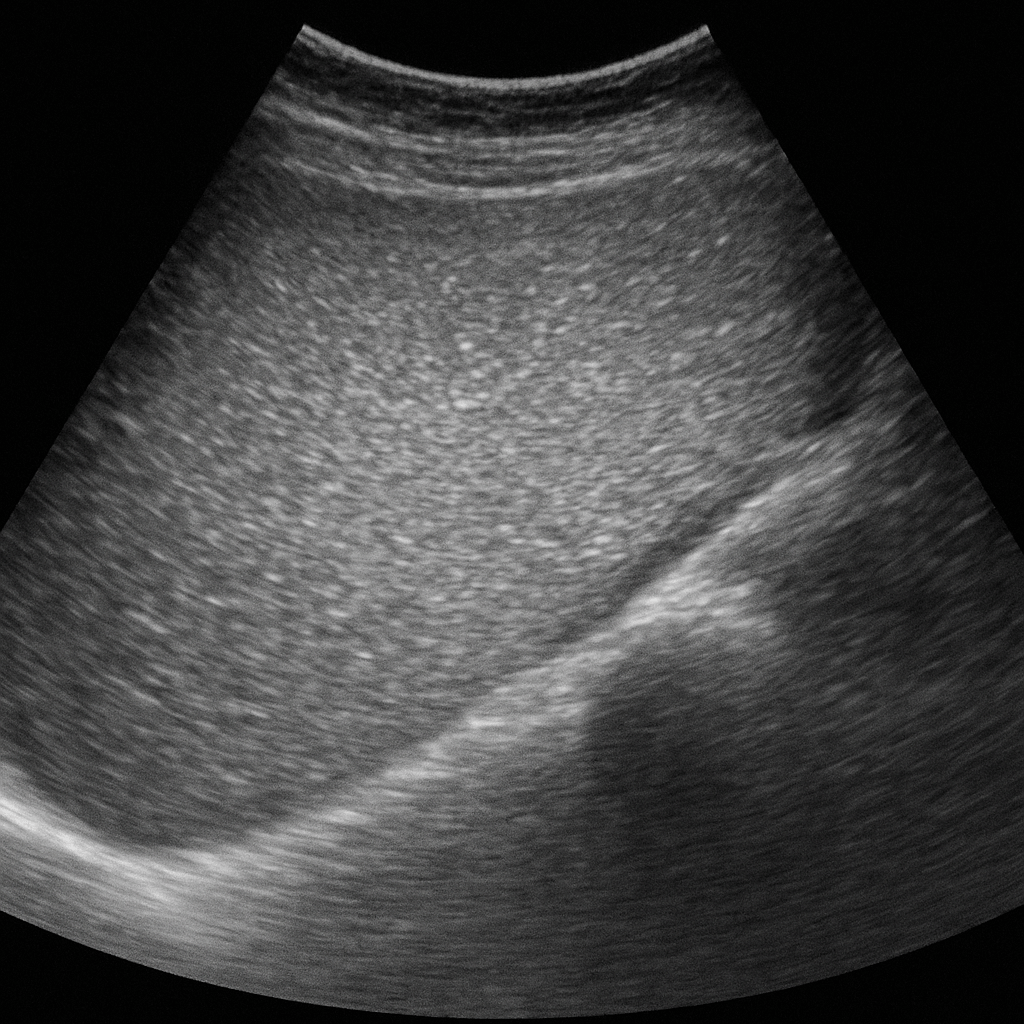

- 간초음파에서 ‘밝게 나오는’ 소견 (에코 증가)

정기적인 혈액검사와 간초음파는 지방간의 진행 여부를 판단하는 데 핵심적인 역할을 합니다.